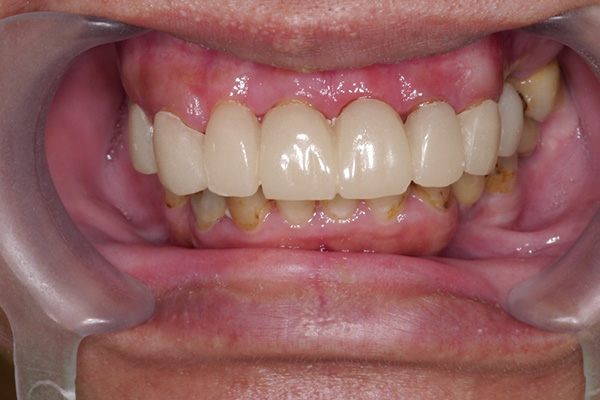

牙周病初期治療(無手術,治療前)![]() |

牙周病初期治療(無手術,治療後)![]() |